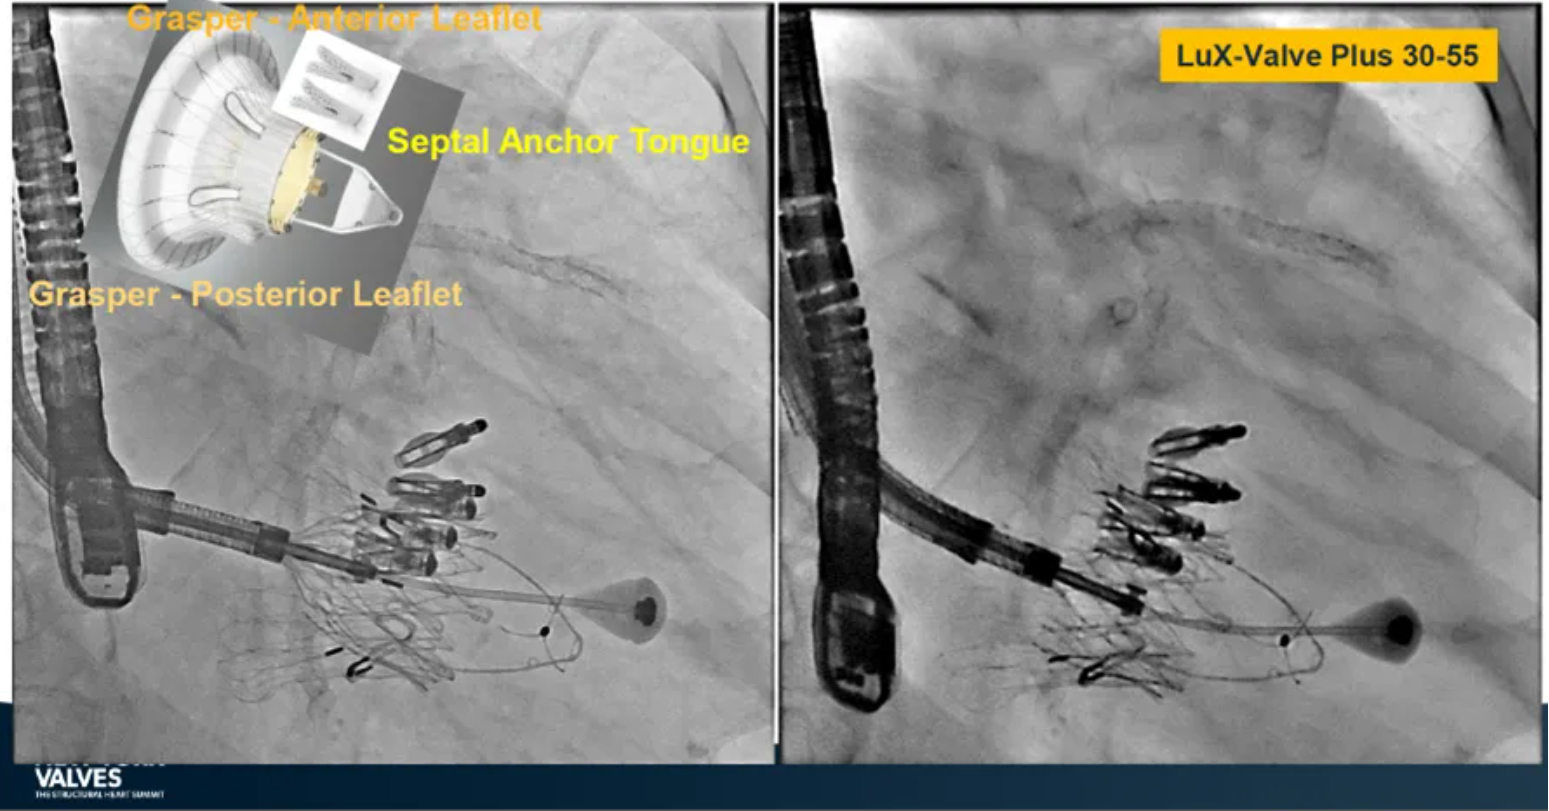

LuX-Valve Plus是健世科技(Jenscare,9877.HK)推出的全新一代經(jīng)頸靜脈三尖瓣置換系統(tǒng)(Transjugular Tricuspid Valve Replacement System),其創(chuàng)新性地采用頸靜脈作為手術(shù)入路,在不依賴徑向支撐力的情況下借助室間隔錨定、瓣葉夾持技術(shù)構(gòu)成其多重錨定結(jié)構(gòu),并通過自適應(yīng)編織環(huán)有效進(jìn)行心房側(cè)封堵,呈現(xiàn)更好的安全性和有效性。

近期,由Juan F. Granada教授在2024紐約瓣膜會(New York Valves 2024)上,以及葛均波院士牽頭發(fā)起,聯(lián)合周達(dá)新教授和陸方林教授在第十八屆東方心臟病學(xué)會議和世界心臟病學(xué)大會(OCC-WCC 2024)上,全球公布了LuX-Valve Plus的TRAVLE II 臨床試驗(yàn)研究6個(gè)月期隨訪結(jié)果,備受與會專家學(xué)者的關(guān)注。